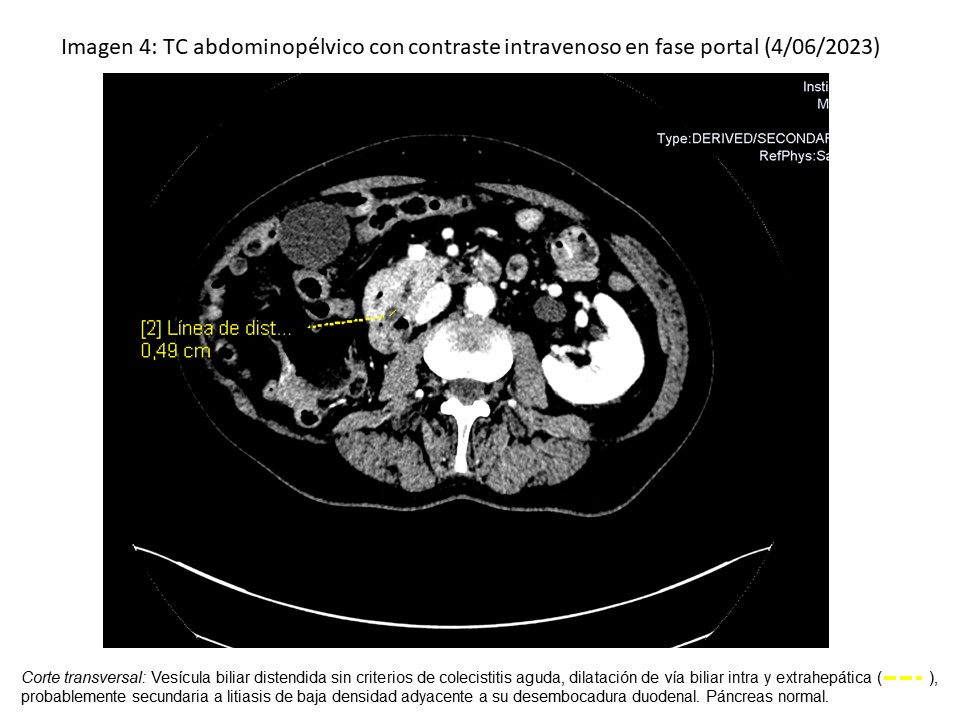

• TC abdominopélvico (4/06/2023): dilatación de vía biliar intra y extrahepática, por litiasis.